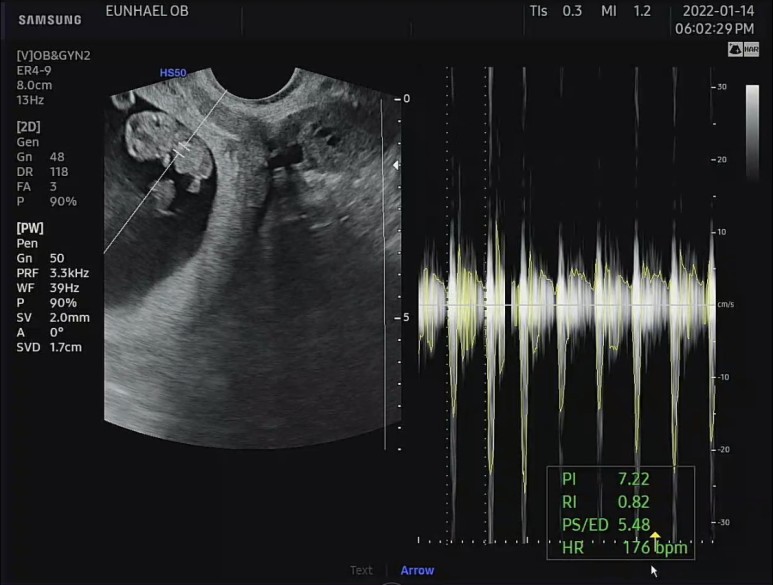

심장소리 듣기.

박동수도 우렁차서 175~177bpm을 왔다갔다.

9주 무렵 태아의 평균 심장박동수는 155~195bpm이라고 한다. 정상 성인보다 훨씬 빨리 뛰는 것이 정상임! 아주 평균치의 박동수를 보여주고 있는 건강한 우리 아가. 참 감사하고 또 감사하다. 우렁찬 쿠구 쿠구 박동소리 들으니 또 맴이 찡.. 기특하다 기특해.